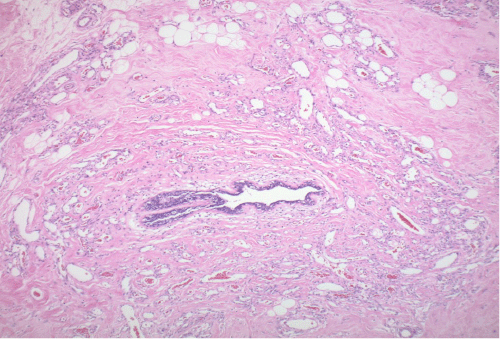

Figure 3. Representative Pathology Following Complete Resection. Published with Permission

A) 4x: H&E stain with increased cellularity and vasculature infiltrating ductal breast tissue

B) 10X: H&E stain demonstrating anastomosing vessels

C) 40x: H&E stain demonstrating endothelial atypia

D) Ki-67 immunohistochemistry demonstrating increased mitotic activity